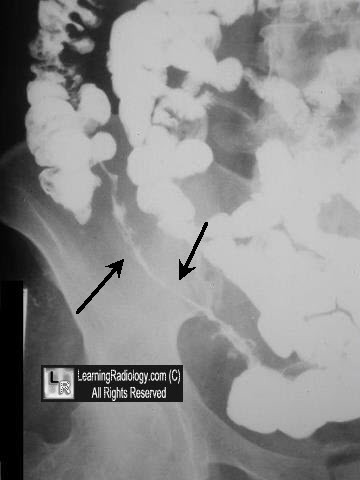

String sign of Kantor

RIF string like strictures on barium studies

Crohn’s disease